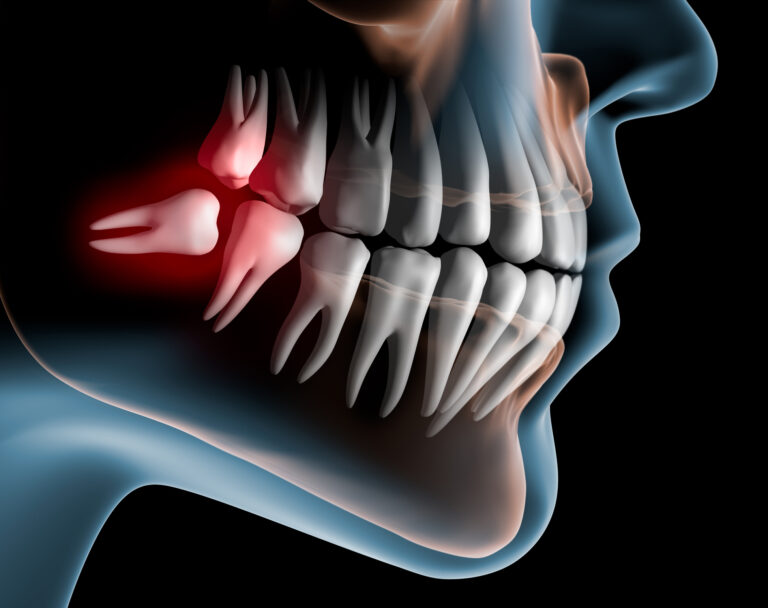

Most people are not fortunate to have them positioned in ideal location or angulation. Dentists refer to these as “impacted”.

Pericoronitis is the name of a condition where there is inflammation and / or infection surrounding the soft tissue around a partially erupted tooth and if this keeps recurring during your lifetime it is likely in your best interest to have the teeth that cause it to be removed.

Wisdom teeth may or may not grow completely or partially through your gums.

1. If you have impacted or non functional wisdom teeth which are potentially compromising the health of teeth nearby,

2. If you have chronic, recurrent pericoronitis (that is, if you keep having aches and pains from the wisdom teeth which arise because food debris accumulates in areas which are hard to clean).